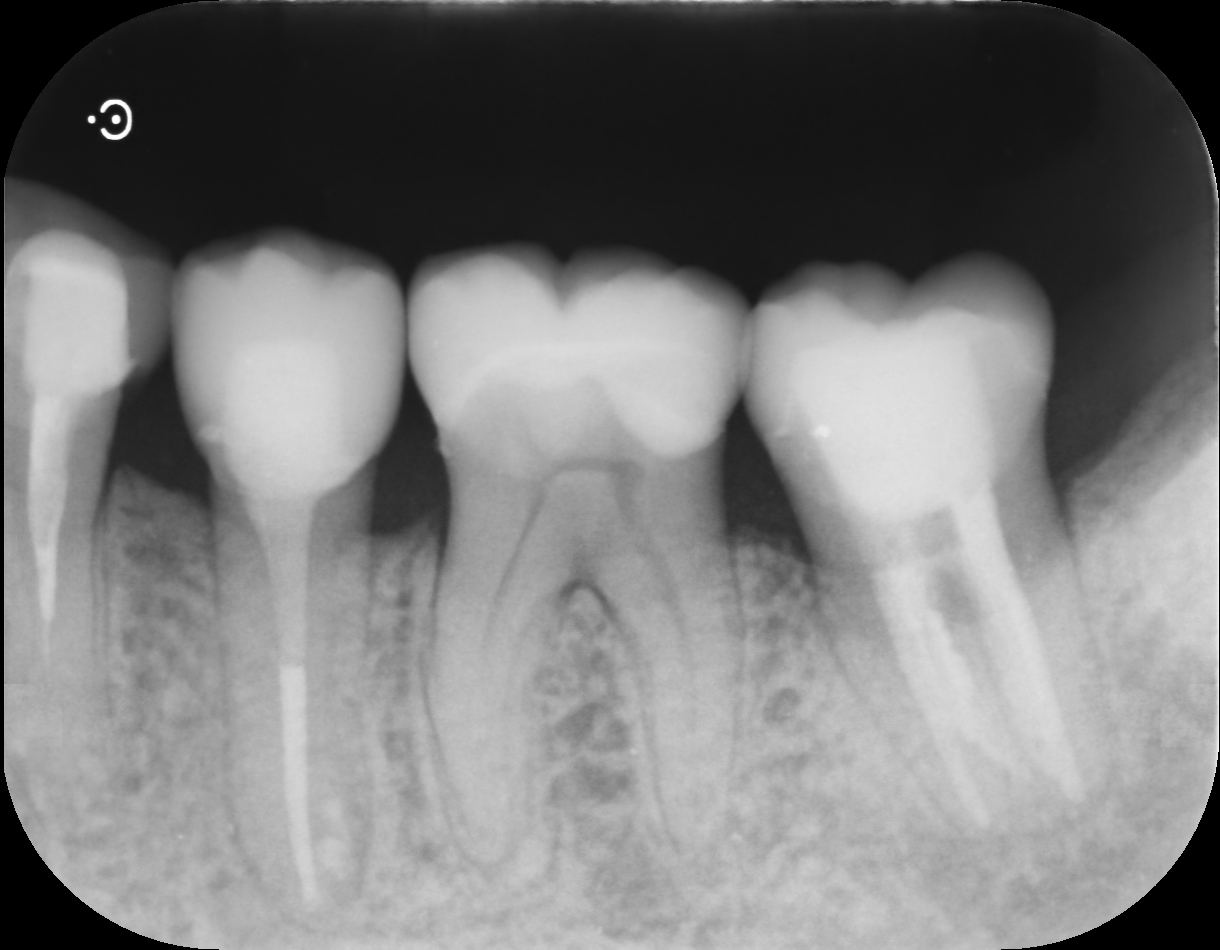

• before

歯肉の腫れの原因である感染した歯の神経や細菌を取り除くため、根管治療を行いました。

歯の内部の根管内を専用の器具で清掃・消毒し、細菌が残らないように洗浄を繰り返します。

根管内が清潔になったことを確認した後、薬剤を充填し、最終的に被せ物などで歯を補強します。

左下第二小臼歯・第二大臼歯 根尖性歯周炎

根管治療、補綴治療